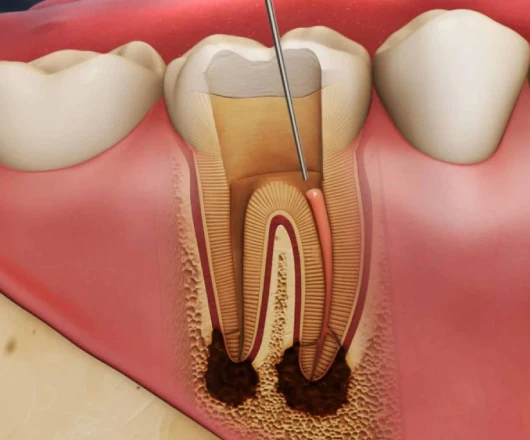

- Canal Cleaning: The infected part is cleared away, and the channels are sanitised to ease pain.

- Shaping & Sealing: Rotary instruments shape canals before sealing them against reinfection.